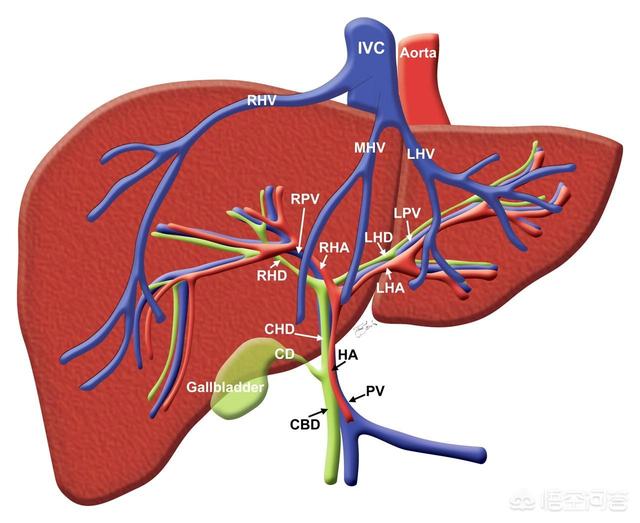

肝臓は、私たちの体の中で最も大きく、最も複雑な働きをする臓器のひとつである。

まず、糖質、タンパク質、脂質の三大栄養素の代謝に関与する;

次に、胆汁の分泌であるが、この点は忘れてはならない。私たちの体には胆嚢という臓器があるが、胆汁は胆嚢から分泌されるのではなく、肝臓から分泌される。胆嚢は胆汁を貯蔵し、濃縮し、食べ物を消化するために必要な時に排出する役割しかない;

第三は代謝で、体内の多くの物質の代謝に関与している;

第四に、いくつかの代謝産物の解毒や排泄といった生体内変換作用である。

肝臓は人体最大の化学工場であり、分泌機能を持つ最大の臓器である。肝臓は生体内変換、排泄、分泌、解毒、ビリルビン代謝を担い、三大栄養素(糖、脂肪、乳、タンパク質)、ビタミン、ホルモンの代謝にも関与している。

肝機能は主に代謝で、体の化学工場であり、外来毒素や代謝老廃物は肝臓で分解されるが、糖、タンパク質、脂質などの代謝にも関与し、免疫、凝固などの機能もある。

3、肝臓は私たちの体の物質代謝である。ハブ"体のほとんどすべての器官と機能に影響を及ぼす。

糖代謝炭水化物(糖質)は、身体が主に燃焼機能として利用する栄養素である。血中グルコースを一定の生理的濃度範囲に維持することは、全身の重要な臓器の生理的機能を確保するために不可欠である。そして血糖値がこれほど安定するのは、肝臓が血糖値の調節にダイナミックな役割を果たしているからである。

タンパク質代謝。アルブミン、フィブリノゲン、凝固因子など、ほとんどすべての血漿タンパク質は肝臓に由来する。 肝機能が低下してアルブミンの合成が低下すると、血漿タンパク質濃度が低下する。このような変化は、肝臓病の診断や治療効果、予後の判定に間接的に役立てることもできる。これがひとつで、もうひとつは肝機能が低下し、凝固因子の合成が少なくなり、ビタミンKの吸収が悪くなり、凝固異常も起こりうるということだ。

脂質代謝と解毒脂質は人体にとって重要な栄養素であり、エネルギーの貯蔵や機能性に大きな役割を果たす。肝臓は、脂質の代謝において中心的な役割を果たしている。肝疾患患者の多くが脂質異常を起こしやすいのはこのためである。それが1つ、2つだ。肝臓は、さまざまな外因性薬物、毒素、ホルモンなどの内因性物質を生体内変換する主要な部位であり、関与する可能性のある生化学反応は数え切れないため、肝機能の低下はその機能を果たす能力にも直接的な影響を及ぼす。解毒。

ビリルビン代謝肝疾患の患者の中には、皮膚や目が黄色い人がいることも冒頭で述べた。ビリルビンの代謝が悪くなっている証拠だ。私たちはこれを専門用語で「黄疸」と呼び、ビリルビンは肝臓が中心的な役割を果たすことなく生成、輸送、結合、代謝されることに注目している。